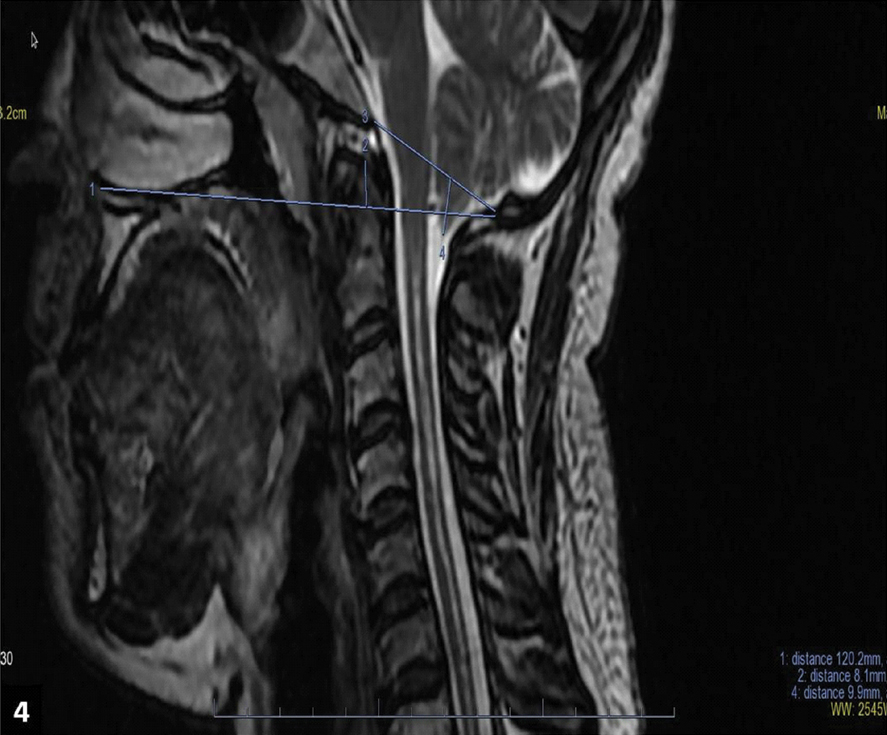

MRI of the spine revealed long segment syrinx from C2 to D4 vertebral body level. Tip of odontoid process was about 8 mm above Chamberlain’s line. Pointed peg of tonsil was about 9 mm below the foramen magnum [Table/Fig-4]. Based on above clinic radiological profile, diagnosis of neuropathic shoulder joint secondary to Chiari Malformation type I associated with syringohydromyelia was made. Patient was referred to Neurosurgery department for decompression of syrinx and was put on conservative management in the form of limb immobilisation and splinting of the joint. Later, patient was advised physiotherapy in the form of ultrasonic therapy, shoulder muscle strengthening and range of movement exercises. Patient gradually improved strength and range of movement following three months of treatment.

Sagittal T2 weighted image shows long segment syrinx, pointed peg of tonsils at foramen magnum and basilar invagination.